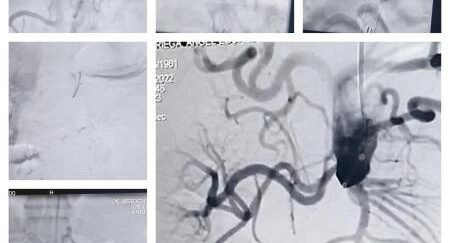

El Dr. Sergio Ludueña explicó: “Nosotros ingresamos por el brazo hasta la ingle derecha con catéteres y cuerdas. Los elementos van abriendo el paso para dilatar con balones en forma progresiva, y posteriormente se le coloca la endopróteisis para impermeabilizar la aorta. Con esto generamos un eje de flujo hacia la pierna derecha”.

“Una vez que se abre eso, se realiza un bypass que va a cruzar a la otra pierna para lograr una perfusión que permita mejorar la calidad de vida del paciente, mejorando la circulación en sus extremidades, ya que el paciente se encuentra en silla de ruedas”, afirmó el hemodinamista del INCOR.